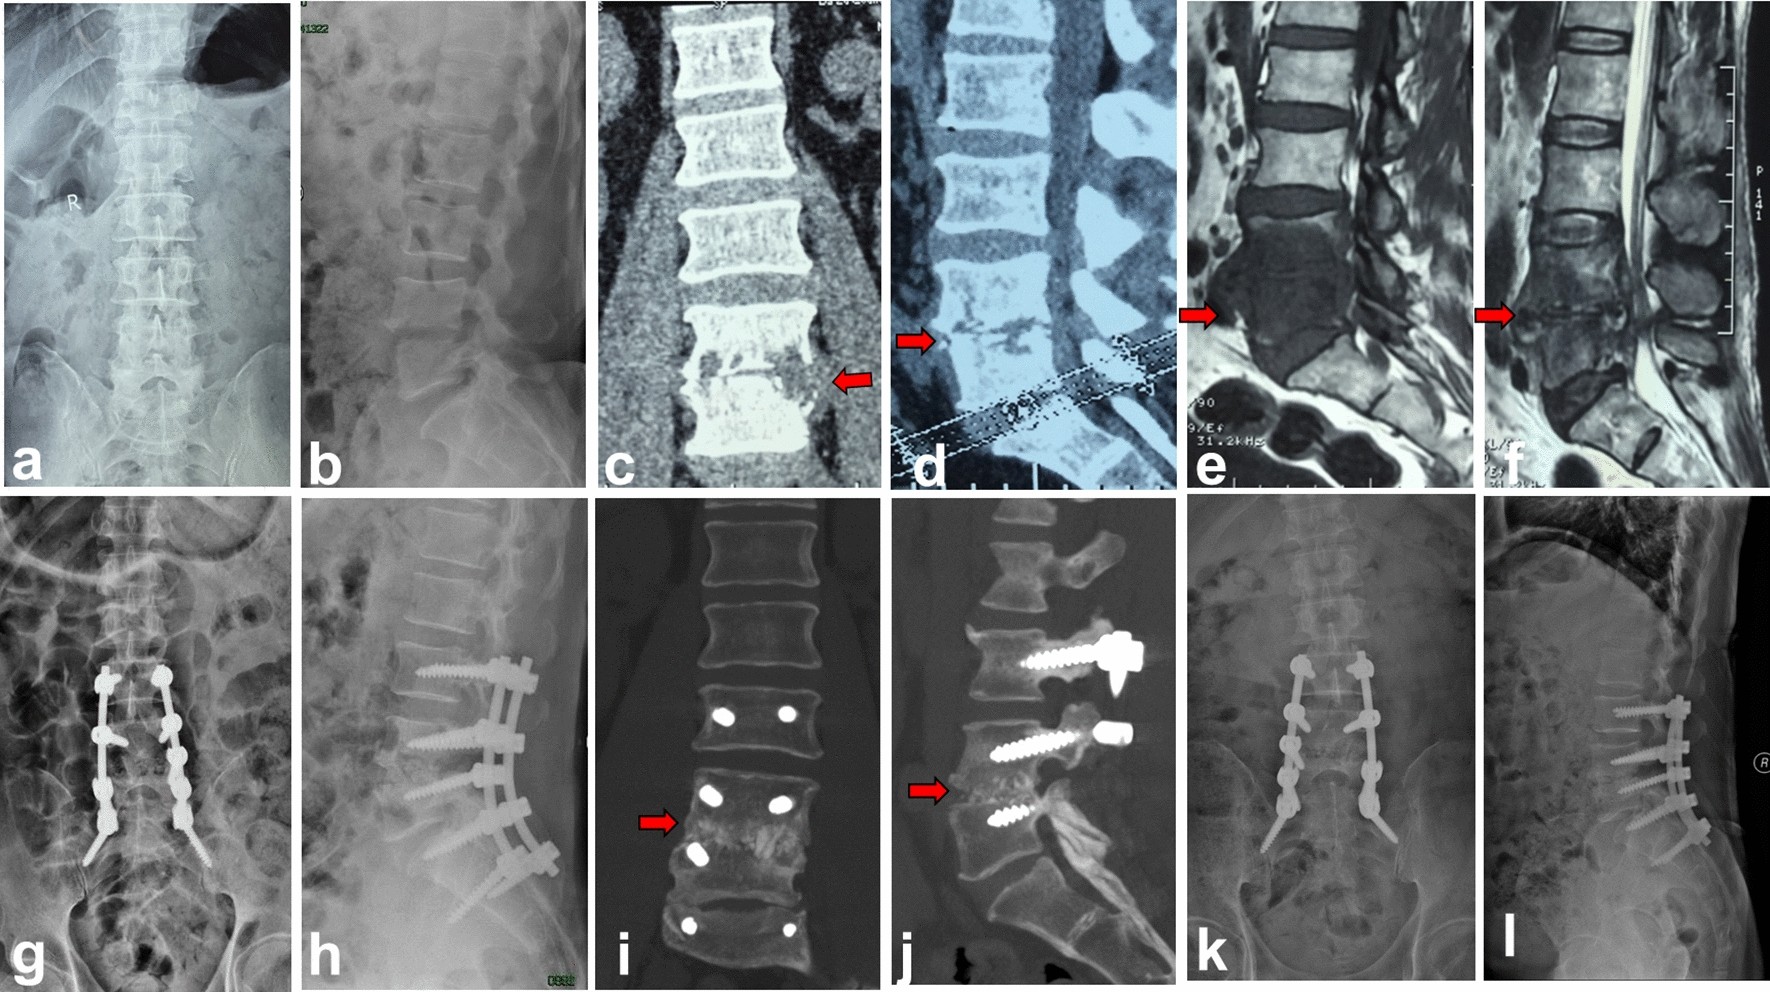

Figure 4

Autologous spinous process group (group B). A 62-year-old male with L4–5 lumbar pyogenic spondylitis. (a–f) Preoperative MRI and CT showed there were bone destruction, intervertebral space stenosis and massive paravertebral abscess (red arrow) at L4–5. (g,h) Postoperative X-ray showed autologous spinous process, screws and rods were in good location. (i–l) CT taken at 5 months after operation showed solid bone fusion between L4 and L5.